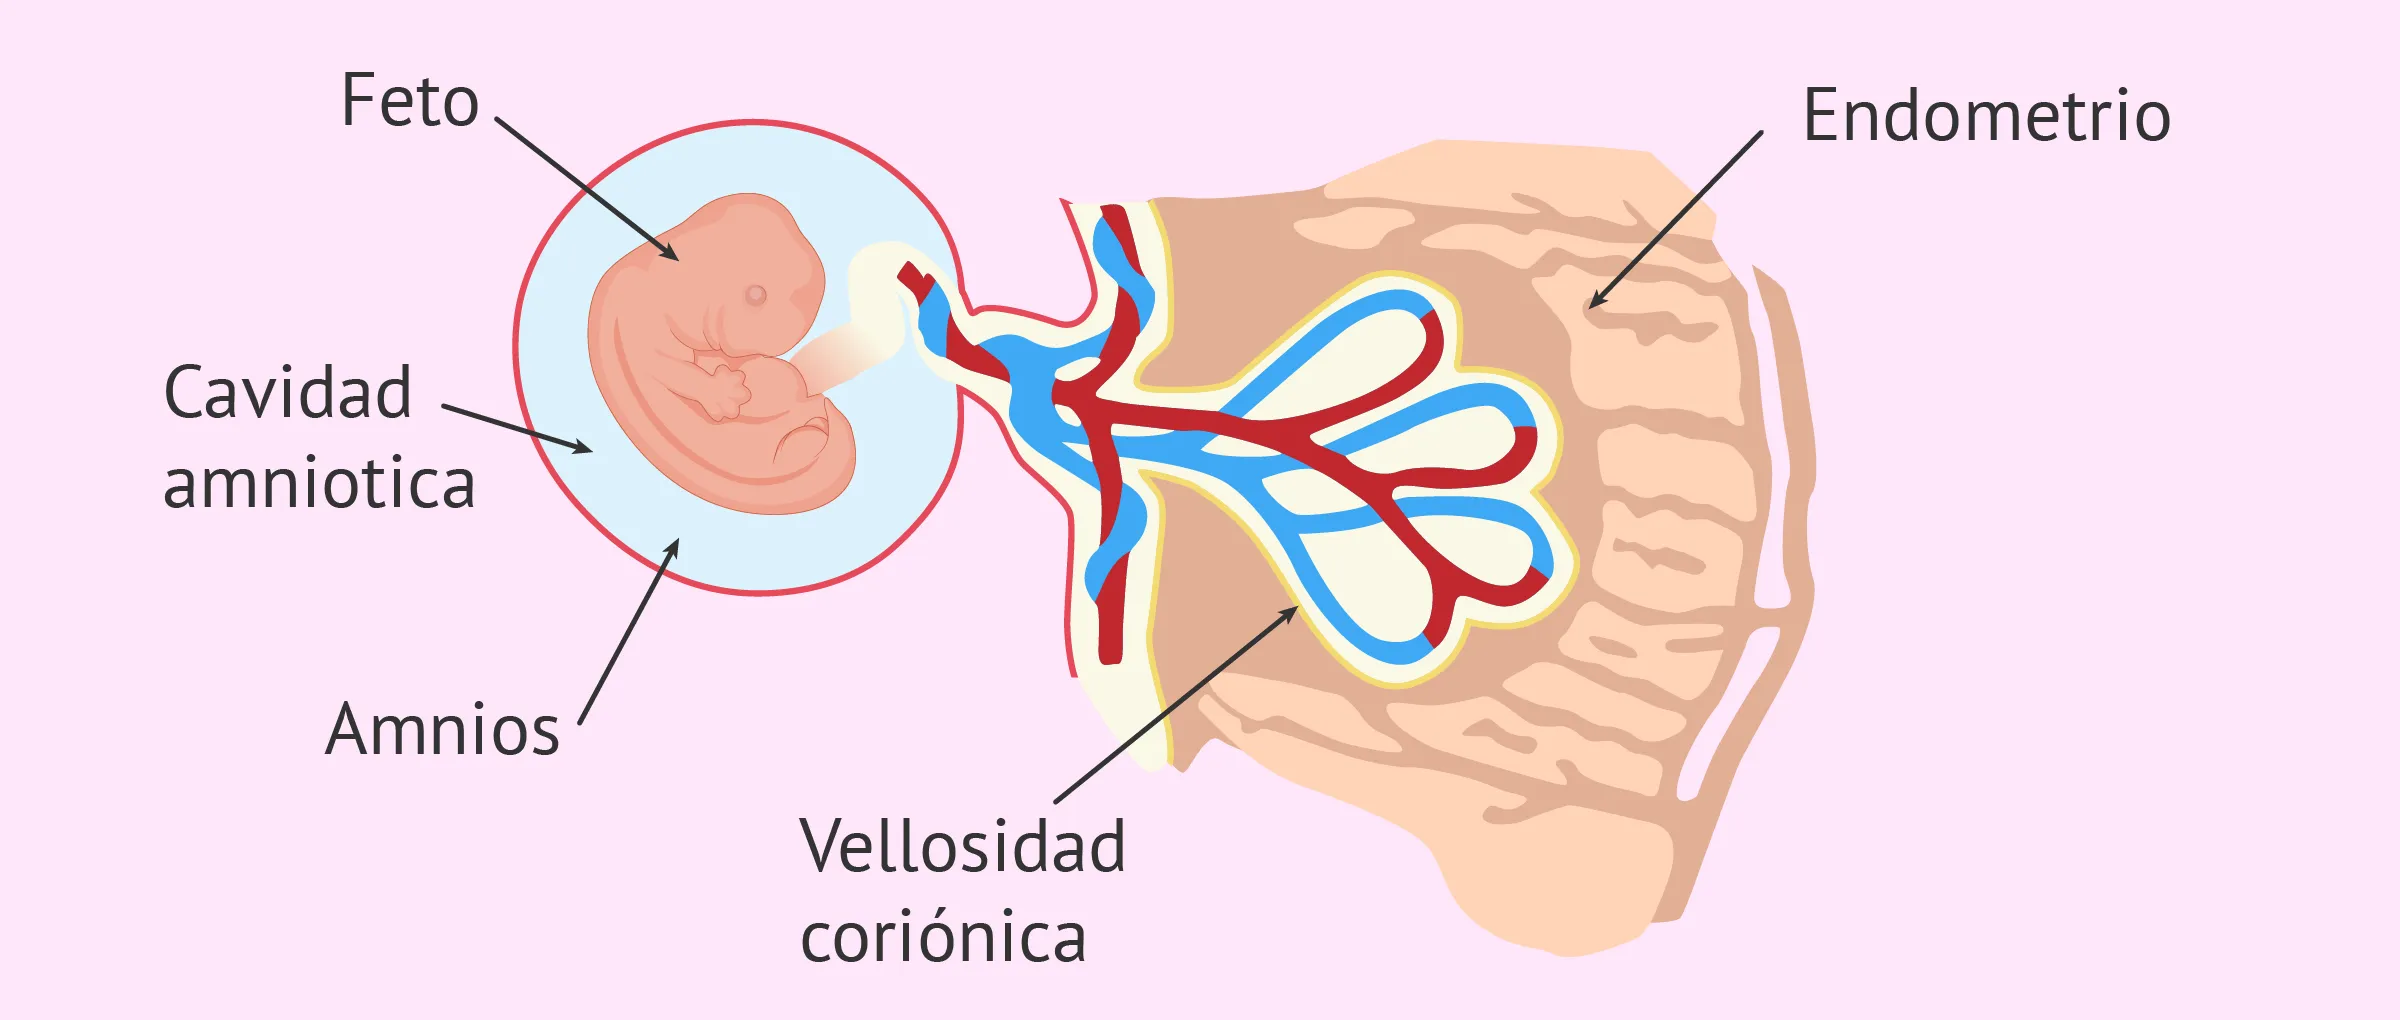

Semana 4 de embarazo: cambios, síntomas y consejos

Semana 4 de embarazo: implantación del embrión en el útero